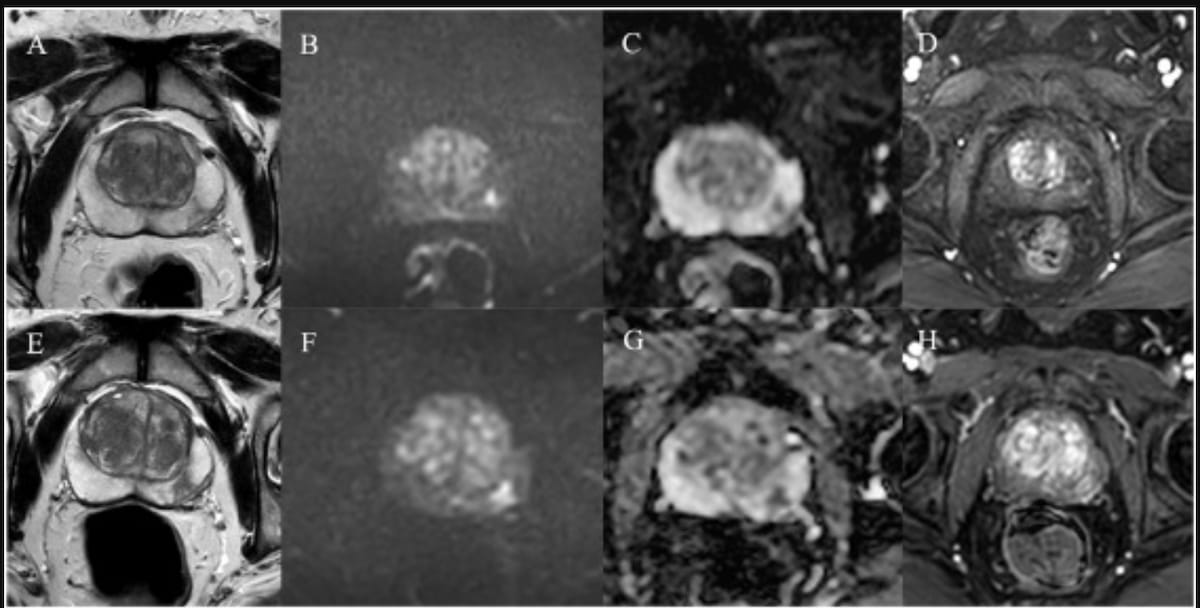

Abbreviated biparametric MRI demonstrated nearly equivalent detection rates for clinically significant and clinically insignificant prostate cancer as multiparametric MRI, according to research involving 22 centers in 12 countries.